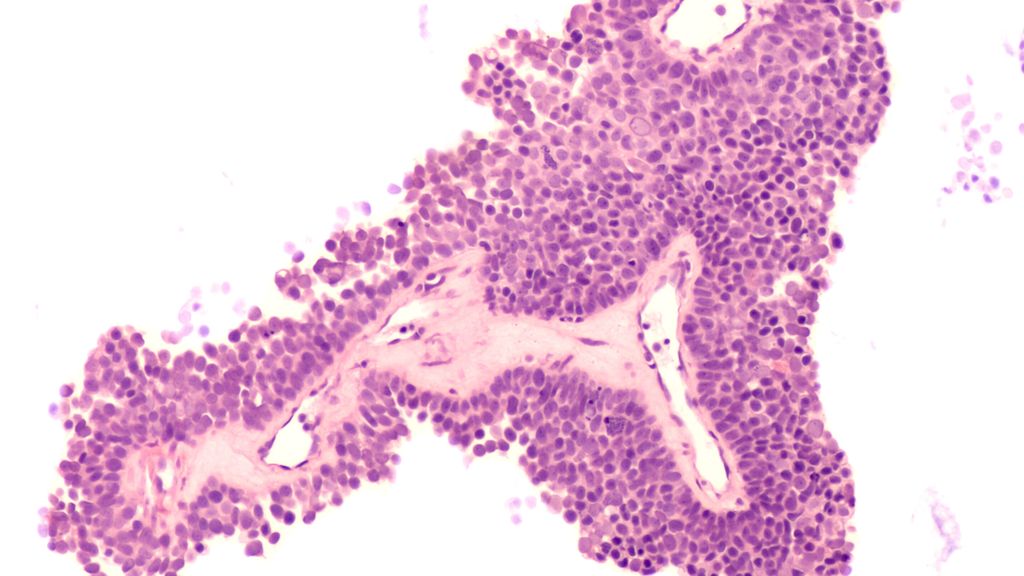

Dans le domaine des tumeurs gastro-intestinales, des progrès ont été réalisés, en particulier dans le traitement des patient·es atteint·es d’adénocarcinome de l’estomac et de la jonction ...